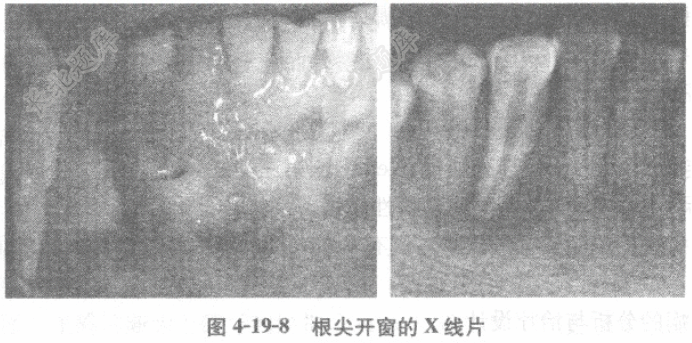

松动(-)、叩(-),临床牙冠长度正常。44牙冠变色,冷热诊(-),叩(-),根尖开窗,根尖暴露。X线片显示44根尖有透射区,边界不清,无骨白线(图4-19-8)。